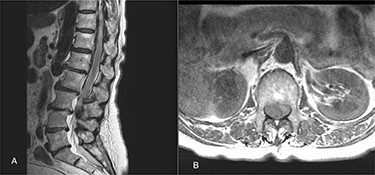

On 17 February 2020, she underwent TKA (Fig. 1). Spinal anesthesia was performed, with the patient in sitting position with one laborious puncture, as referred by the anesthesiologist. The patient received low molecular weight heparin (4000 UI enoxaparin sodium) subcutaneously 12 h after the surgery and a second shot dose 24 h later. On the second post-operative day (19 February 2020), early in the morning, the patient complained of numbness in her lower extremities and low back pain, partially relieved with analgesics. Four hours later, she was complaining for severe difficulty in moving her legs with increased low back pain. The physical examination showed flaccidly paralyzed left lower leg (0/5 left quadriceps, 0/5 left extensor digitorum longus, 0/5 left tibialis anterior and 0/5 left extensor hallucis longus), marked motor function reduction of the right lower leg (1/5 right quadriceps, 2/5 right extensor digitorum longus, 2/5 right tibialis anterior and 2/5 right extensor hallucis longus), sensory loss in both lower limbs, Babinski sign negative bilaterally and preserved sphincter functions. Magnetic resonance imaging (MRI) was required to rule out an acute spinal compression. The images showed a spindle-like mass, mostly intradural, from T11 to L3, hypointense in T2 and heterogeneous in T1 images compressing the dural sac (Fig. 2). Therefore, a diagnosis of acute spinal hematoma was made, and the patient was transferred to the Neurosurgery Department, and surgical decompression was scheduled. A bulky blood clot was removed through a spino-hemilaminectomy of T11 and T12 followed by a posterior dural incision. The source of bleeding was identified in a perimedullary vein on the dorsal surface of the spinal cord that was coagulated. Surgery was performed 3 h after diagnosis, and few hours later, the patient was able to perform a flexion-extension of both lower limbs. She was able to start walking with a walker 24 h later. A low molecular weight heparin (2000 UI Enoxaparin sodium) subcutaneously was started 1 week after surgical decompression. This dosage was increased to 4000 UI 2 days later. On 24 February 2020, a follow-up MRI was performed, and it showed a partial resolution of the hematoma with a confined area of myelopathy at the T12 level (Fig. 3). On the 26 February 2020, the patient started the rehabilitation protocol with the gradual improvement of the neurological status.

(A) The sagittal T2 FSE MRI show hypointense spindle-like mass from T10 to L3; (B) axial T1w FSE MRI showed iso-hyperintense hematoma compressing the dural sac (L1 level).

The clinical importance of this disorder is due to its sudden compressive effect on the spinal cord. The signs and symptoms are not different from other pathologies that can lead to acute compression of the spinal cord (tumor, trauma or vertebral abscess). In a patient with severe lumbar pain, acute or subacute, with a uni- or bilateral radicular pain, a spinal hematoma must be rule out [12]. If misdiagnosed, it may have catastrophic consequences. An early recognition is essential, and MRI is a sensitive imaging tool to confirm the suspicion. Findings on MRI depend on the timing of appearance of the clot: in the first 24 h, the hematoma is usually isointense on T1- and is hyperintense on T2-weighted images; after 24 h, it becomes hyperintense on T1 and on T2 [13].